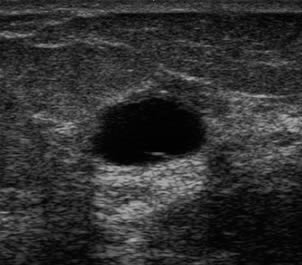

Bild vergrößern

Ultraschall einer Zyste in der Brust